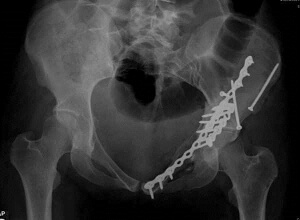

Следующая стадия лечения — иммобилизация. При необходимости проводится операция, цель которой — закрепление в нужном положении обломков костей. При повреждении кольца таза, медицинские работники проводят скелетное вытяжение. Терапия изолированных или краевых переломов заключается в положении пациента в гамаке или на щите.

Если имеется более одного перелома таза или если перелом повреждает ткани, человека следует оперировать как можно скорее. Для этого можно использовать метод внешней фиксации для стабилизации тазовых мышц. Во время этого метода внутри мышцы прикрепляются металлические штифты или винты, делая небольшие надрезы.